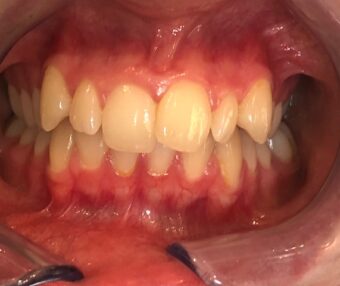

Patient want to straighten and whiten her teeth in a discreet way so we started her Invisalign journey and completed it in 5 months. We then done some composite bonding to make the canines less pointy to complete the look the patient desired !